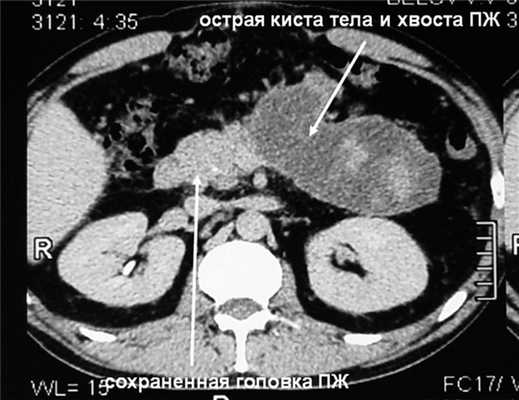

К середине этих же суток на фоне быстрого повышения ВБД до 28 мм рт.ст., что сопровождалось еще более значительным увеличением объема живота, возникли анурия и гипотензия с АД 75/40 мм рт.ст. Начато внутривенное введение дофамина в увеличивающихся дозах, максимально 12 мкг на 1 кг массы тела в 1 мин - без эффекта, затем - адреналина в дозе 0,15 мг на 1 кг массы тела в 1 мин, чем удалось стабилизировать АД на уровне 125/75 мм рт.ст. Проявления дыхательной недостаточности значительно усугубились - на фоне принудительной исскуственной вентиляции легких 100% кислородом индекс оксигенации снизился до критического уровня, составив 115 (нижняя граница нормы 350). Уровни мочевины и креатинина в сыворотке крови в это же время повысились до 32 ммоль/л и 298 мкмоль/л соответственно. Таким образом, на 3-и сутки заболевания и лечения у больного с субтотальным некрозом ПЖ и обширным некрозом забрюшинной жировой клетчатки отмечена развернутая картина прогрессирующей ПОН с недостаточностью функции четырех органов или систем (легких, почек, головного мозга, сердца и сосудов), что произошло на фоне ВБГ III степени. Диагностирован АКС, в связи с чем пациенту экстренно выполнили фасциотомию путем рассечения апоневроза по белой линии живота от мечевидного отростка до лонного сочленения без вскрытия брюшины из двух небольших кожных разрезов длиной по 3 см. Через 30 мин после операции ВБД снизилось с 28 до 19 мм рт.ст., а через 4 ч - до 14 мм рт.ст., после чего восстановился нормальный темп диуреза, показатели гемодинамики позволили прекратить инфузию адреналина, была уменьшена дыхательная поддержка. На 2-е сутки после операции ВБД снизилось до 8 мм рт.ст., на 3-и сутки - до 5 мм рт.ст. и впоследствии не повышалось. Суточный диурез составлял 2-2,5 л, показатели мочевины и креатинина крови к 5-м суткам после декомпрессии брюшной полости снизились до нормы. Постепенно индекс оксигенации повысился до нормальной величины, на 6-е сутки после операции больной был переведен на режим вспомогательной вентиляции, а через 10 сут после фасциотомии - на самостоятельное дыхание. Швы с ран сняты в срок, зажили первичным натяжением. Фазу инфекционных осложнений ОДП удалось миновать путем комплексной профилактики, включающей внутривенное введение тиенама в дозе 3 г в сутки, энтеральное зондовое питание и селективную деконтаминацию желудочно-кишечного тракта. На 14-е сутки лечения больной переведен в хирургическое отделение. Необходимости выполнения чрескожных диагностических и лечебных вмешательств под контролем УЗИ, а также хирургической некрсеквестрэктомии не возникло. В области некротизированных тела и хвоста ПЖ образовалась острая псевдокиста размером 17×7×7 см, параколит регрессировал (см. рис. 3, б). Рисунок 3. Компьютерные томограммы больного Б. б -перед выпиской. Через 29 сут лечения больной был выписан.

Госпитализирован через 3 мес в плановом порядке (рис. 4). Рисунок 4. Вид передней брюшной стенки того же больного перед грыжесечением. При компьютерной томографии (рис. 5) Рисунок 5. Компьютерная томограмма того же больного перед грыжесечением. киста уменьшилась в размерах до 12×5×4 см, начинает замещаться рубцовой тканью, клинические проявления ее отсутствуют, признаков сахарного диабета и экскреторной недостаточности ПЖ нет.